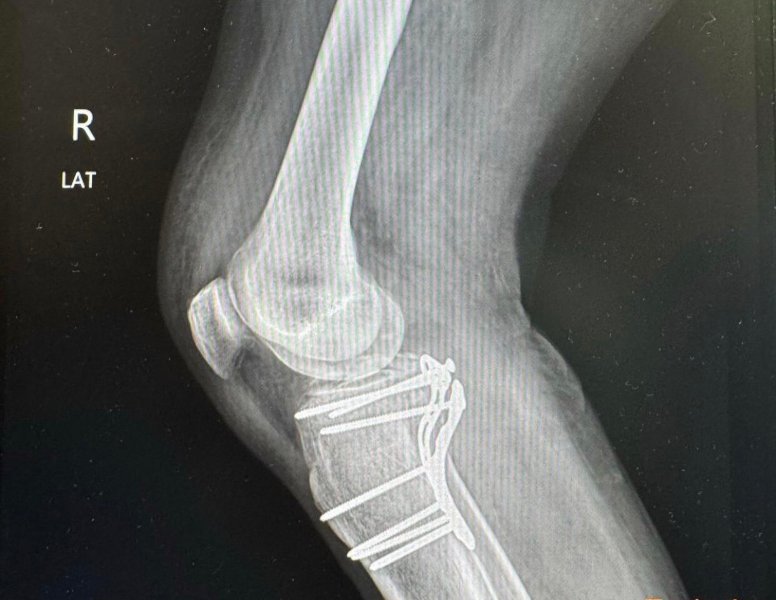

My gf is a travel guide. She has a bunch of Slovaks as customers. She packed them off at their hotel at 8pm and at 8pm she is on her own time. One of the daft <deleted> got a motor bike to go somewhere or other and crashed. Broke two ribs and both legs. She has been asked to go to the hospital to help out but her credit is maxed and can't get cash. Can I send her some cash. Isn't that the responsibility of the dumb stupid Slovaks. What is the betting they have no insurance. Sending cash for Thai families is one thing. I draw the line at dumb stupid tourists.